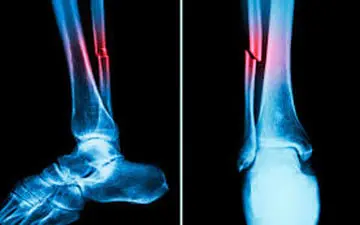

برای تشخیص و درمان جوش خوردگی استخوان، نیاز به یافتههای بالینی و رادیوگرافی و در اغلب موارد نیز نیاز به مداخله جراحی…